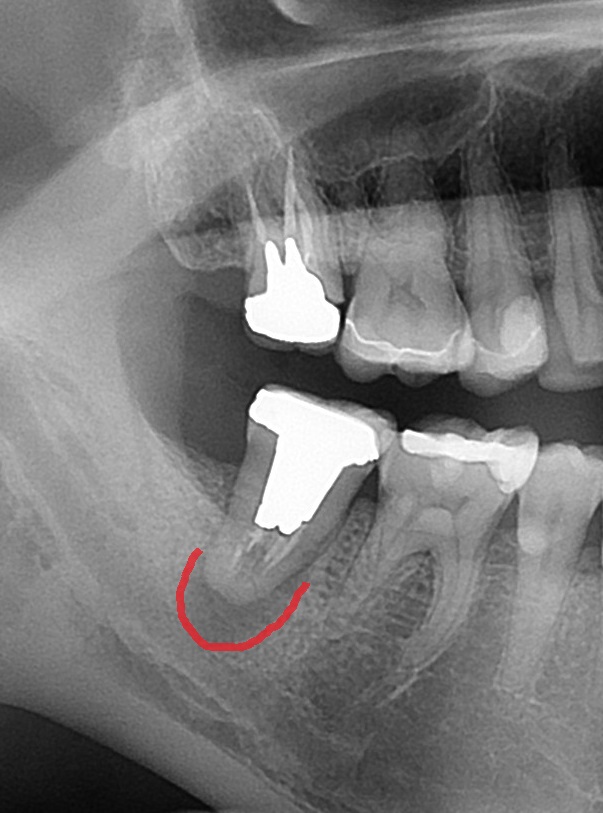

レントゲン写真を撮ってみると、

右下7番目の歯です。根っこの中に白いスジがあり、神経治療がされています。

そして、赤い枠の中が黒く抜けて見えます。膿で顎の骨が溶けています。